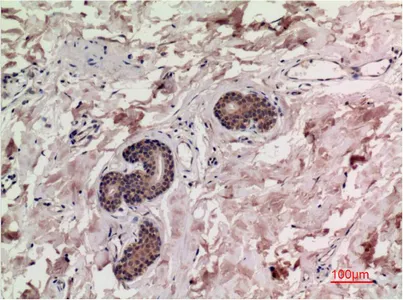

CK7(12D7)Mouse Monoclonal Antibody

Cat: AMM08857

Size1:50μl Price1:$128

Size2:100μl Price2:$230

Size3:500μl Price3:$980

Size2:100μl Price2:$230

Size3:500μl Price3:$980